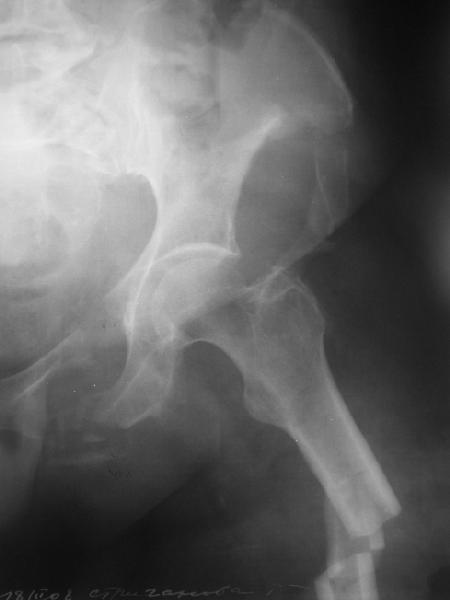

Здравствуйте уважаемые коллеги! Поступила пациентка, 61г, через 1 месяц после травмы, с двусторонним ротационно-нестабильным повреждением тазового кольца: перелом боковых масс крестца с обеих сторон, переломы лонной и седалищной костей слева, отрывные переломы передних остей левой подвздошной кости, сегментарный перелом левой подвздошной кости. Кроме того у пациентки имеется сегментарный перелом левого бедра.

Перелом бедра не вызывает вопросов - планируем блокируемый остеосинтез стержнем, а вот при обсуждении тактики лечения переломов костей таза возник вопрос о необходимости синтеза остей подвздошной кости, учитывая сроки с момента травмы и  наличие остеопороза могут возникнуть технические сложности. Если у кого-нибудь  собственный опыт или ссылки на литературу об отдаленных результатах при не восстановлении сгибательного аппарата бедра?